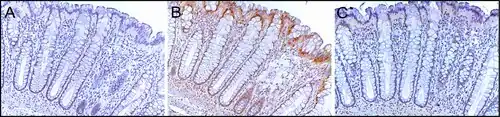

Sequential sections of the same colon crypt with immunohistochemical staining (brown) showing normal high expression of DNA repair proteins PMS2 (A), ERCC1 (B) and ERCC4 (XPF) (C). This crypt is from the biopsy of a 58-year-old male patient who never had colonic neoplasia and the crypt has high expression of these DNA repair proteins in absorptive cell nuclei throughout most of the crypt. Note that PMS2 and ERCC4 (XPF) expression (in panels A and C) are each reduced or absent in the nuclei of cells at the top of the crypt and within the surface of the colonic lumen between crypts. Original image, also in a publication.[27]

PMS2 is usually expressed at a high level in cell nuclei of enterocytes (absorptive cells) within the colonic crypts lining the inner surface of the colon (see image, panel A). DNA repair, involving high expression of PMS2, ERCC1 and ERCC4 (XPF) proteins, appears to be very active in colon crypts in normal, non-neoplastic colonic epithelium. In the case of PMS2, the expression level in normal colonic epithelium is high in 77% to 100% of crypts.[27]

Cells are produced at the crypt base and migrate upward along the crypt axis before being shed into the colonic lumen days later.[28] There are 5 to 6 stem cells at the bases of the crypts.[28] If the stem cells at the base of the crypt express PMS2, generally all several thousand cells of the crypt[29] will also express PMS2. This is indicated by the brown color seen by immunostaining of PMS2 in most of the enterocytes in the crypt in panel A of the image in this section. Similar expression of ERCC4 (XPF) and ERCC1 occurs in the thousands of enterocytes in each colonic crypt of the normal colonic epithelium.

The tissue section in the image shown here was also counterstained with hematoxylin to stain DNA in nuclei a blue-gray color. Nuclei of cells in the lamina propria (cells which are below and surround the epithelial crypts) largely show hematoxylin blue-gray color and have little expression of PMS2, ERCC1 or ERCC4 (XPF).